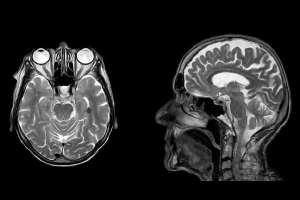

Nuevo malware hace que aparezcan tumores cancerígenos en nuestras radiografías

Un nuevo malware de escáner tomográfico y resonancia magnética es capaz de modificar los resultados, haciendo creer a los médicos que tenemos cáncer.